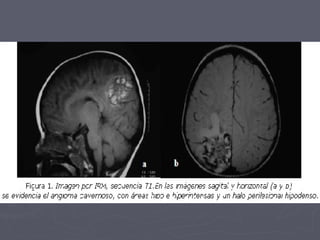

RM: Lesión con aspecto tipo nodular Hipointenso en T1, Rodeado de un Halo de Hemosiderina.

RM: Lesión conaspecto tipo nodular Hipointenso en T1, Rodeado de un Halo de Hemosiderina.